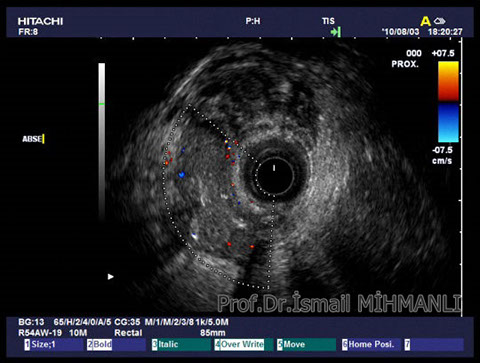

PERİANAL FİSTÜLLER Perianal fistül ve abselerin intersfinkterik anal bez iltihabından kaynaklandığı düşünülmektedir. Crohn hastalarında perianal enflamatuvar hastalık sıktır. İntersfinkterik mesafedeki enfeksiyon yukarıda rektuma, aşağıda cilde, yanlarda dış sfinkteri geçerek iskiyoanal mesafeye uzanabilir. Primer fistülün sfinkterler ile ilişkisini ve abse veya sekonder dal varlığını ameliyat öncesi bilmek, tedavi planı açısından önemlidir. İskiyoanal ve iskiyorektal mesafe tutulmamışsa hastalık daha kolay tedavi edilir. Bu mesafelerde abse veya sekonder bir dal varsa fistül komplekstir ve tedavisi kompleks olmayan fistüle göre değişik olabilir. Bundan dolayı, primer fistül traktı anatomik yerleşimine göre geleneksel olarak sınıflandırılır. Bu sınıflama dörde ayrılır: 1- İntersfinkterik (iç ve dış sfinkter arasında), 2- Transsfinkterik (dış sfinkteri geçerek iskiyoanal veya iskiyorektal mesafeye ulaşmış), 3- Suprasfinkterik (intersfinkterik plandan yukarı doğru uzanan traktüs puborektal kasın Genel Gaz ve Dışkı Kaçırma (Anal İnkontinans) Perianal Fistüller Rektal Tümörler Anal Tümörler Kabızlık Yazılarımız üstündeki bir seviyeden yana kıvrılarak tekrar aşağıya iskiyoanal mesafeye uzanmış), 4- Ekstrasfinkterik (sfinkterlerin dış tarafında rektumdan direkt olarak perianal cilde uzanan traktüs). Endoanal ultrason ile hem primer fistül, hem de varsa sekonder dal ve abse doğru bir şekilde tanınır. Endoanal ultrason ile fistülün anal kanala açılan kısmını (iç uç) görmek kolaydır. Bu hastalarda sfinkter defektlerine de rastlanmaktadır. Sfinkter defekti endoanal ultrason ile kolaylıkla tespit edilir. (bkz. anal inkontinans) Perianal fistül şikayeti olan hastaların az kısmında endoanal ultrason ile bir şey görülemez ise endoanal ultrason probuna ek olarak lineer prob ile anal kanal çevresine bakmak yararlıdır. Çünkü anal kanal bileşenlerinin uzağındaki bir enflamasyon ancak bu problar ile tanınabilir.